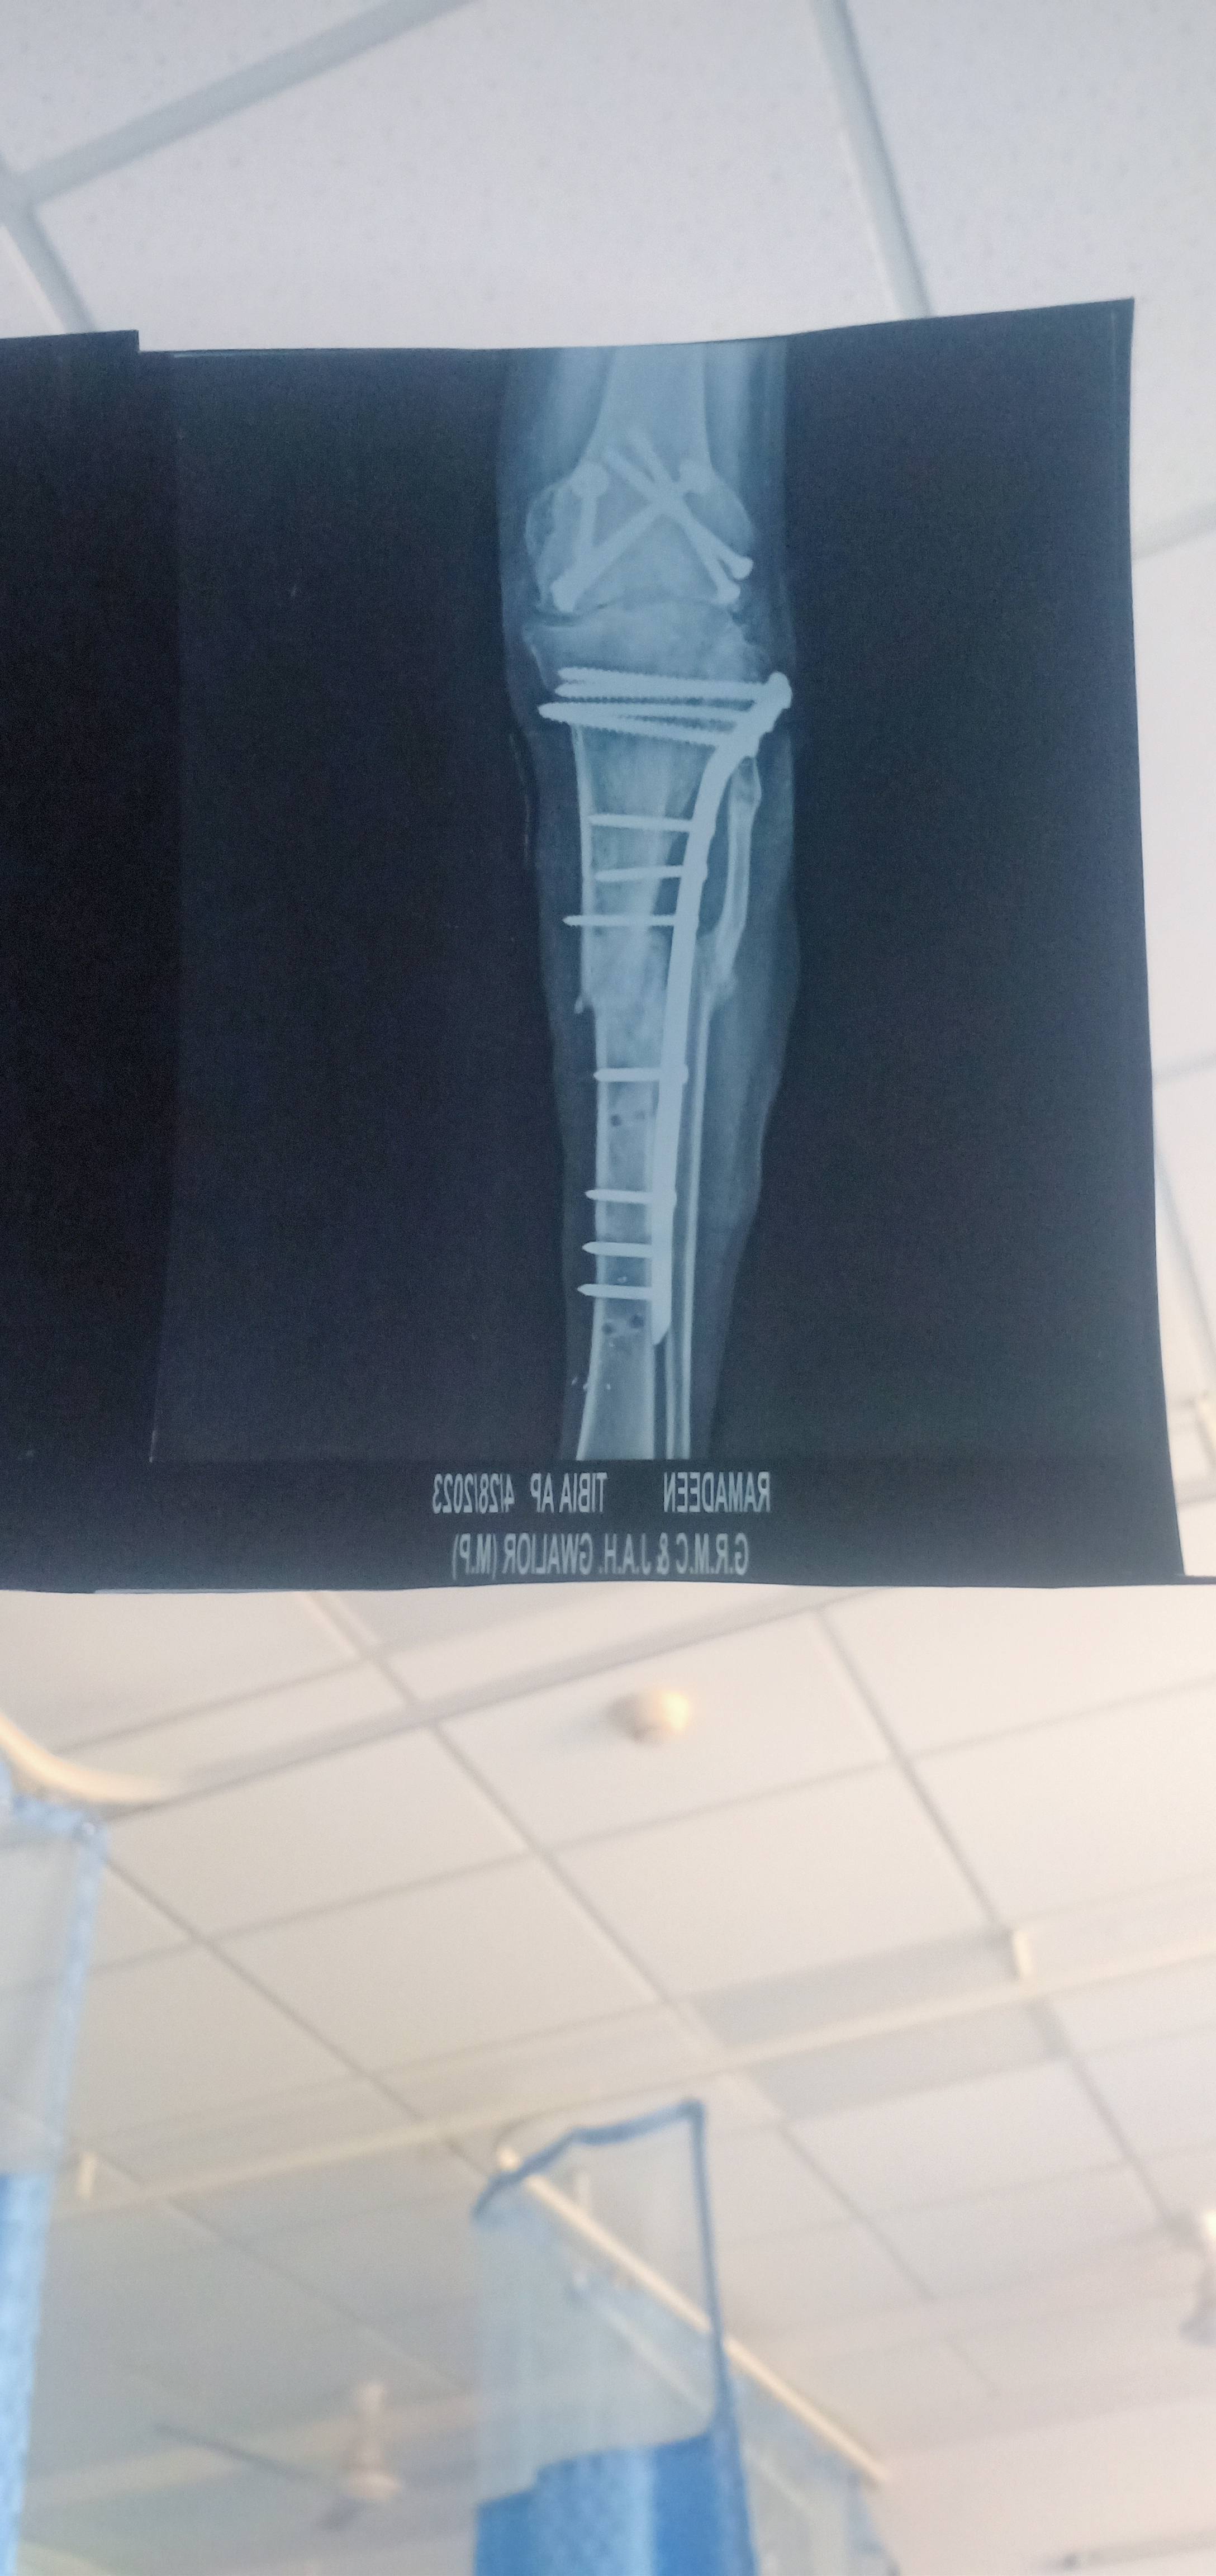

Sir mera problem pair ki Jo toot gyi thi ancle toot gyi hai pehla opration hua tha success nhi hui thi yeh dusra ka operation hua tha usi ki xray kya thik hai xray ancle thik se jood jayega na

Mere pahla fracture 2014 me hua tha jisme open fracture hua tha knee joint ukhad gya tha dusra fracture 8 February 2023 ko hua tha jisme tibia febula fracture tha sir 2014 se knee bend nahi ho raha hai.

please help me ​​​​​